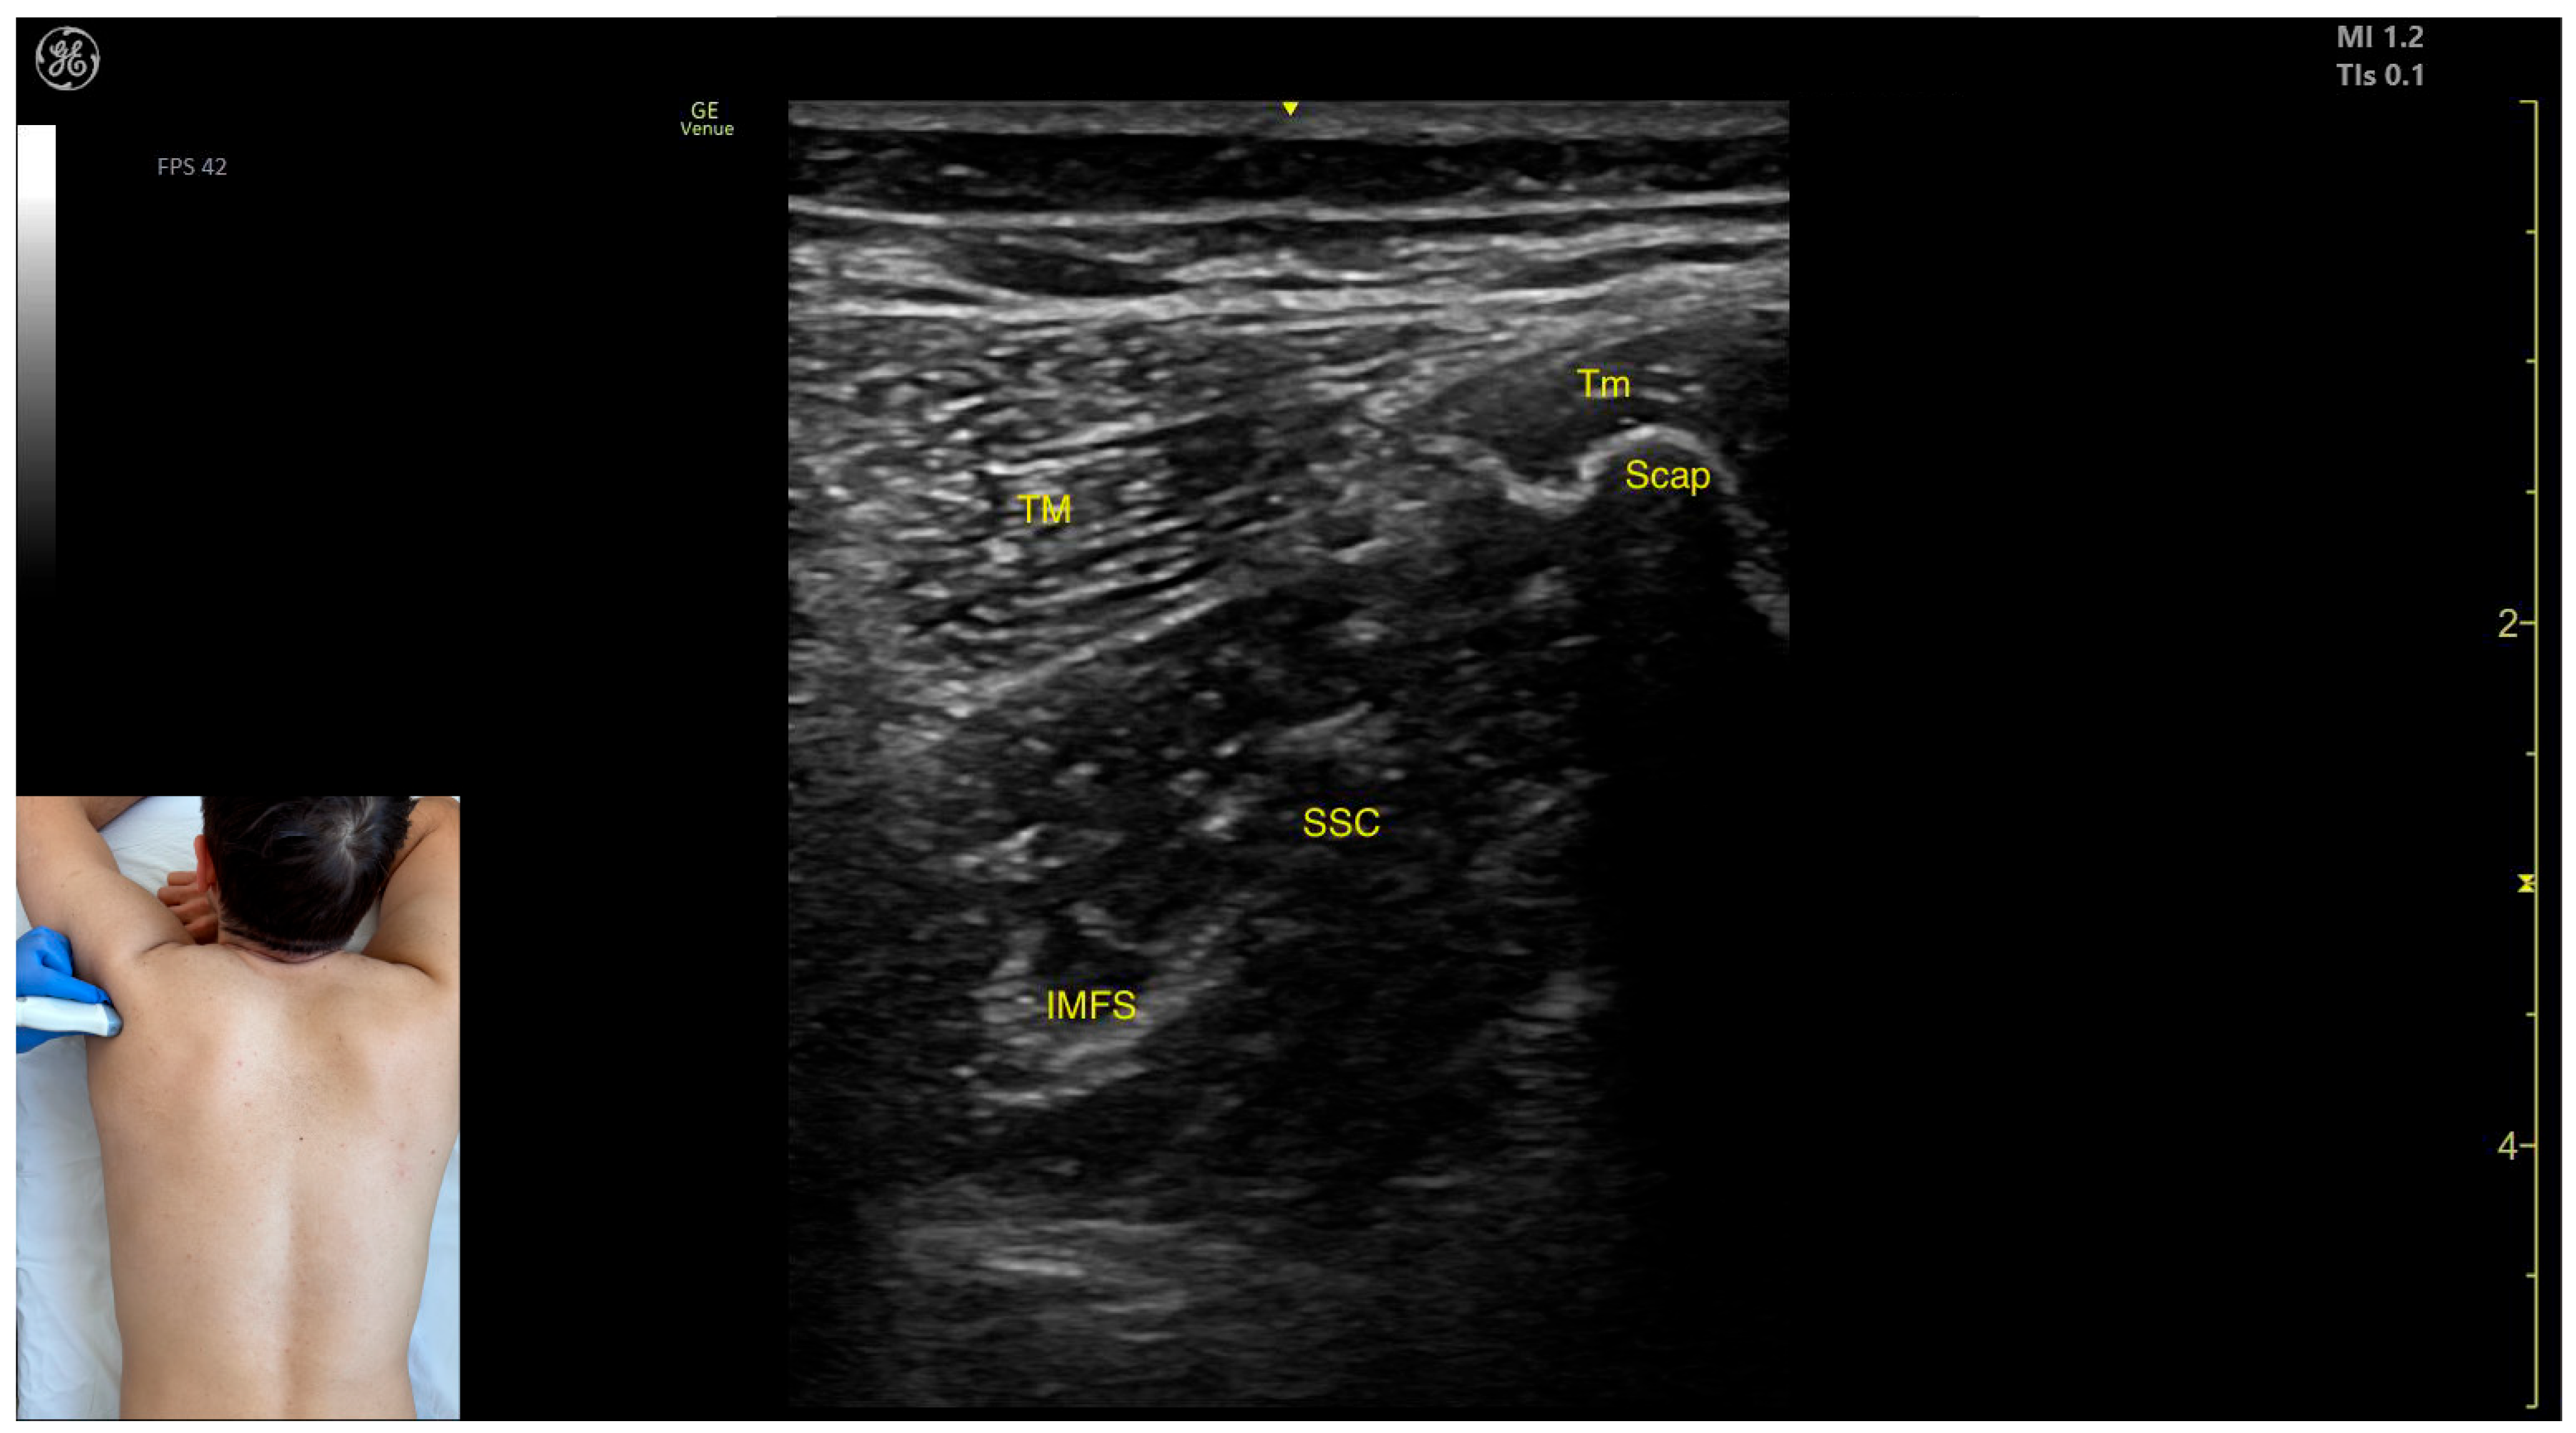

- Muscle position: At this level, the SSC represents the first muscle mass located superficial to the ribs and intercostal muscles. Superficial to the SSC, the TM is observed laterally, and the Tm is observed medially.

- Intramuscular fascial septum: It features an intramuscular fascial septum (IMFS) that separates the muscle into superior and inferior compartments, which can be approached individually if needed.

- External fascia: Unlike other muscles, the SSC does not present a pronounced fascial layer that separates it from the TM during BoNT-A injections.